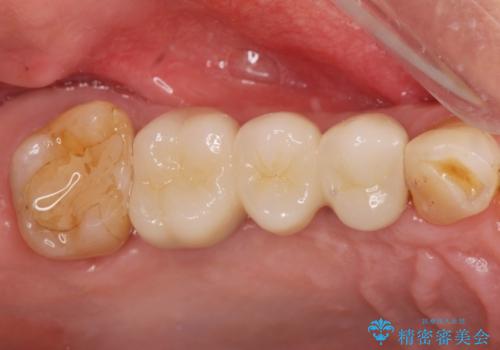

3本の歯が失われた状態を、2本のインプラントで支えるブリッジでの咬合機能回復を計画します。

歯を失ってから長い期間が経過していたので、仮歯が入り咬合機能が回復できた際に大変喜んでいただくことができました。